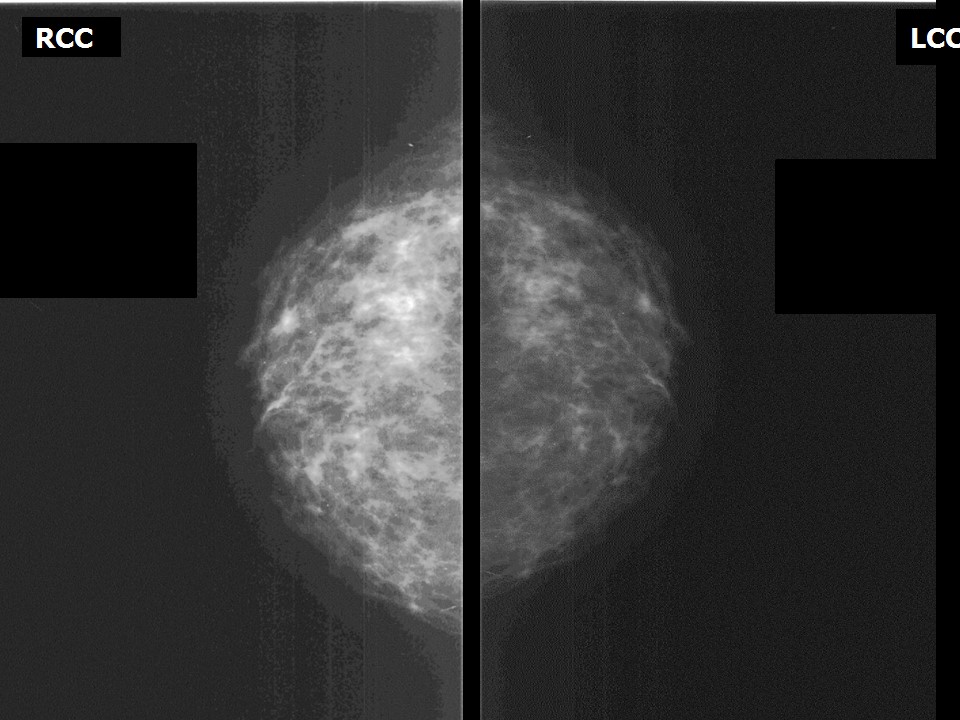

Что такое маммография: важность, процесс и результаты

Раздел: Необычные решения